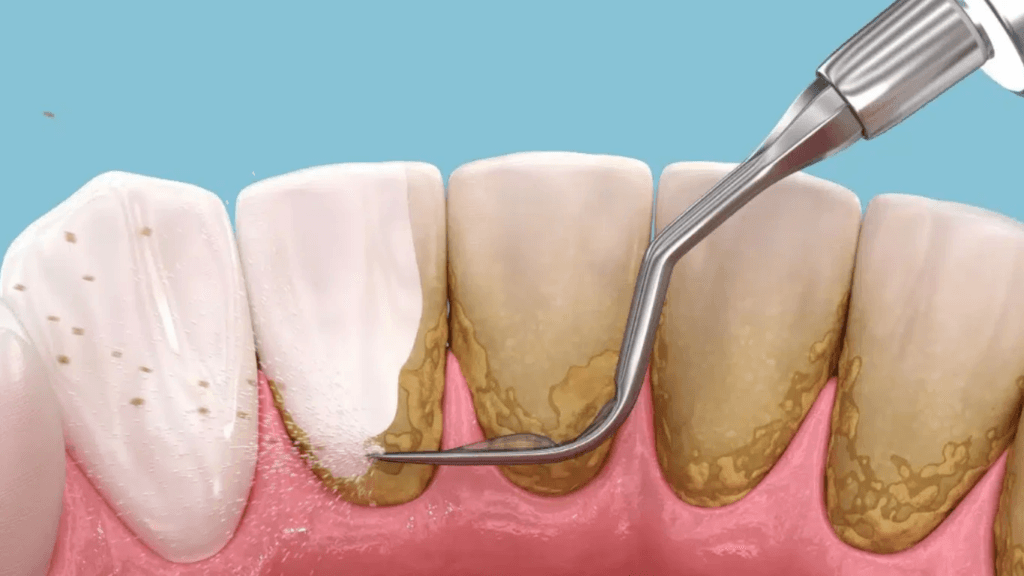

Deep dental cleaning, also known as scaling and root planing, is a specialized dental procedure that goes beyond regular cleanings to treat gum disease and support optimal oral health.This intensive treatment targets the areas beneath the gumline where plaque and tartar accumulate, causing inflammation and potentially leading to tooth loss if not addressed.During a deep dental cleaning, the dentist uses specialized instruments to remove these deposits from the tooth roots and smooth the root surfaces. This helps the gums reattach more effectively to the teeth, promotes healing, and reduces the risk of further damage.

Deep dental cleaning is a vital procedure for treating gum disease, preventing tooth loss, and improving overall oral health. By addressing the underlying cause of gingival inflammation and infection, deep cleaning helps patients maintain healthy gums and teeth, supporting a confident smile and better general health.